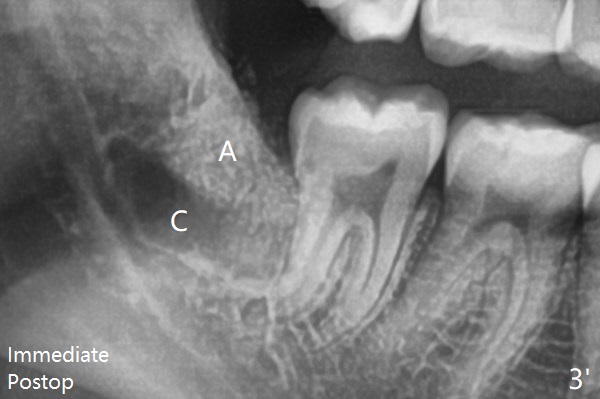

The bone density increases and becomes even at #32 sockets 4 months postop (Fig.4').